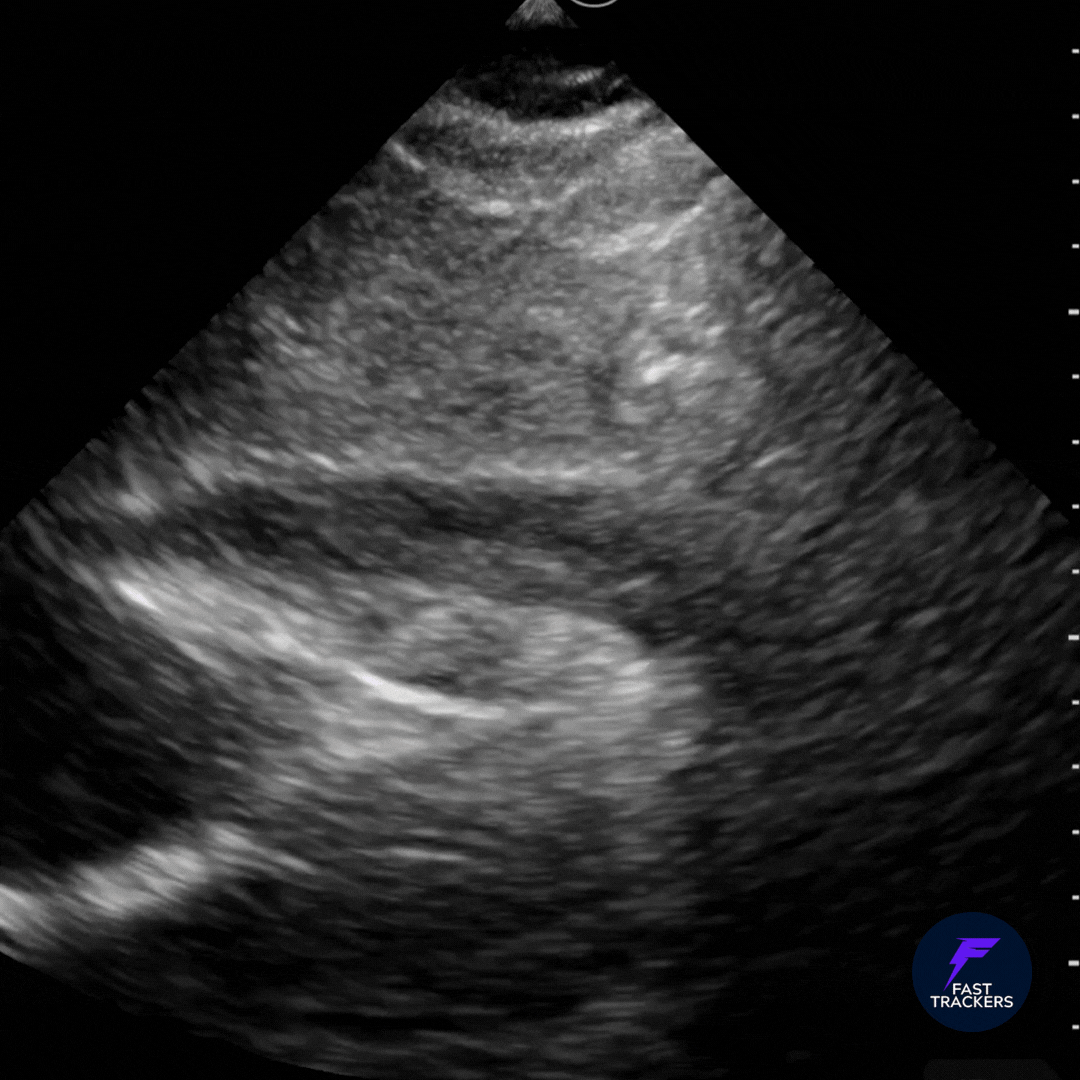

🔴 Épanchement péricardique

• Image anéchogène entourant le cœur

• Visible entre le myocarde et le péricarde

🚨 Signes de tamponnade

• Collapsus diastolique du VD

• Compression de l’OD

• Contexte d’instabilité hémodynamique

Noter le collapsus des cavités droites témoignant d'une tamponnade.